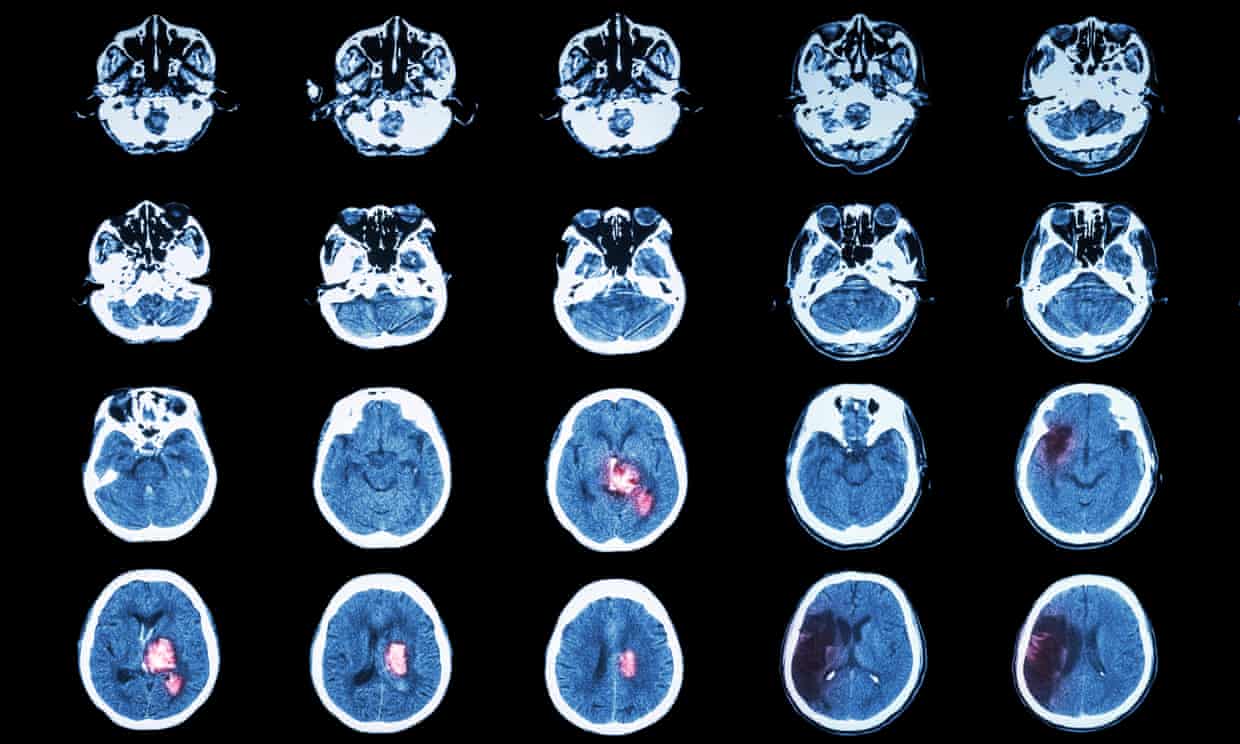

Đột quỵ là một tình trạng y tế nghiêm trọng đe dọa tính mạng xảy ra khi nguồn cung cấp máu cho một phần của não bị gián đoạn. Một số chế độ ăn kiêng nhất định có thể giúp giảm nguy cơ mắc bệnh.

Kết quả chụp mạch máu là căn cứ quan trọng giúp bác sĩ chẩn đoán và theo dõi bệnh lý tim mạch, đột quỵ. Tuy nhiên, nhiều người vẫn băn khoăn liệu những hình ảnh này có thể sử dụng trong bao lâu trước khi cần chụp lại. Thực tế, “giá trị” của kết quả không phải lúc nào cũng cố định, mà phụ thuộc vào diễn tiến bệnh và tình trạng sức khỏe của từng người.